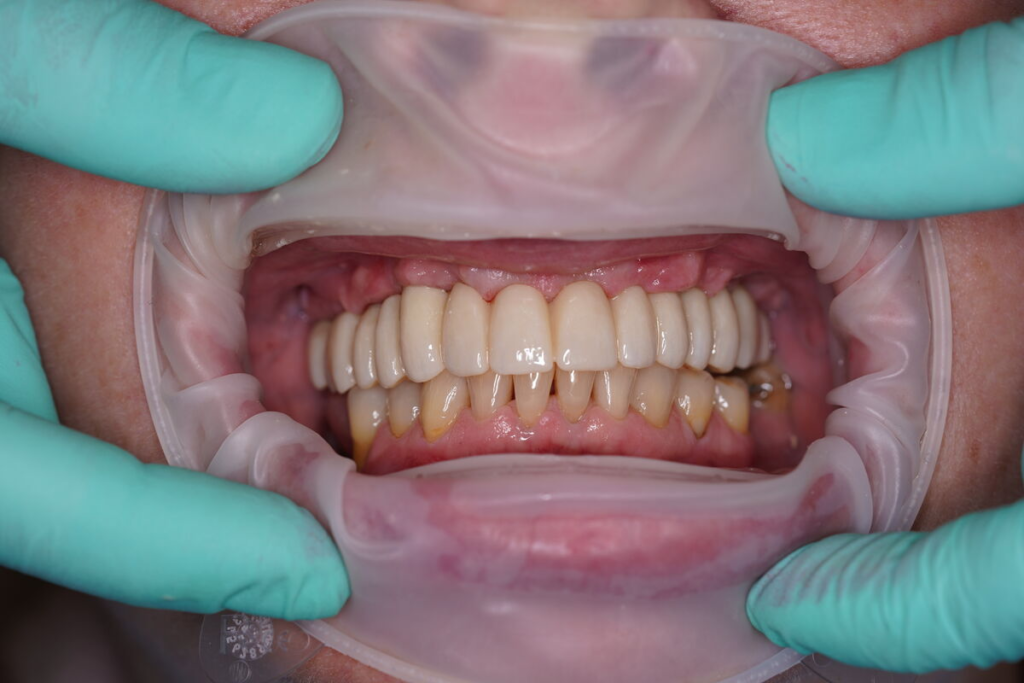

3. Nové zuby tentýž den

Odcházíte s pevnými dočasnými zuby — bez snímatelné protézy.

Můžete mluvit, smát se a jíst měkkou stravu.

Po 4–6 měsících nasazujeme trvalý můstek.

Používáme multivrstvý zirkon pro maximální estetiku, pevnost a dlouhou životnost.

Výsledky, které mluví za vše

- fotografie před/po